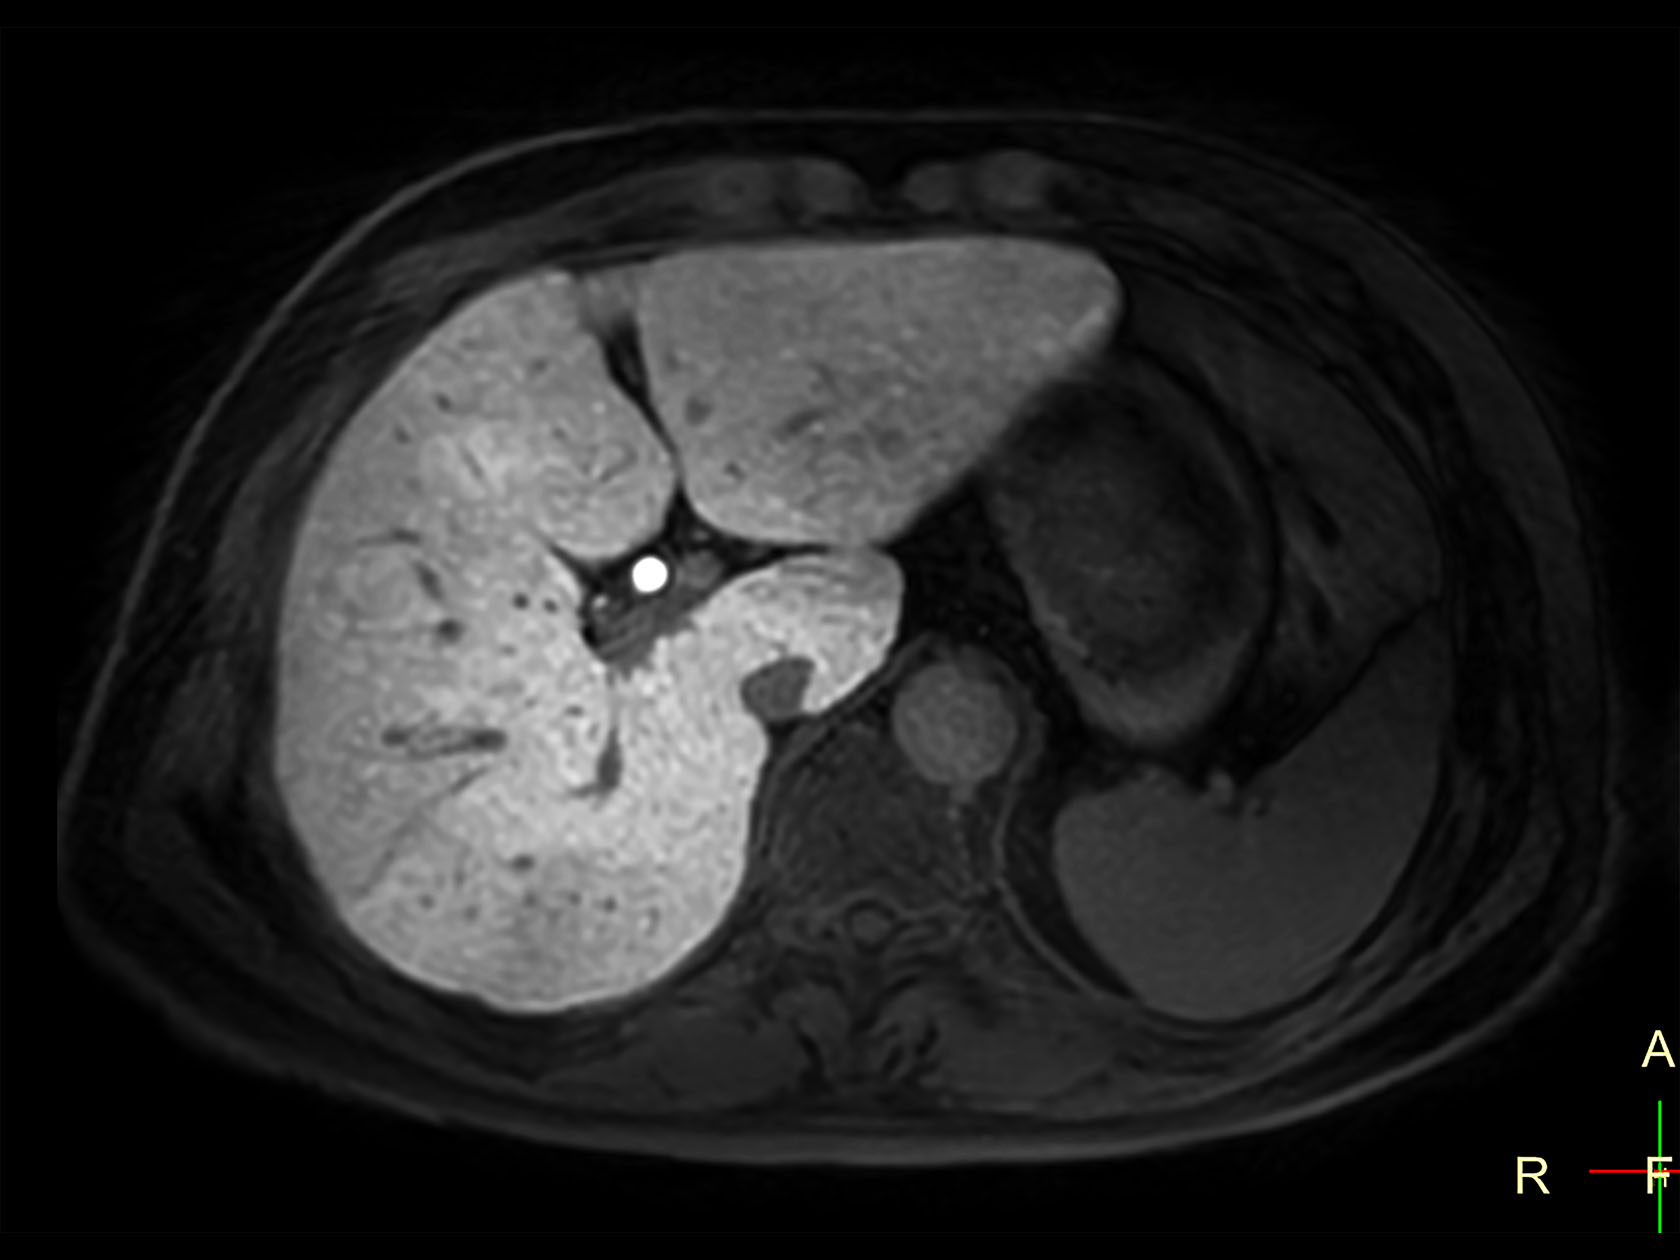

dyn mDIXON XD FFE (pre gado)